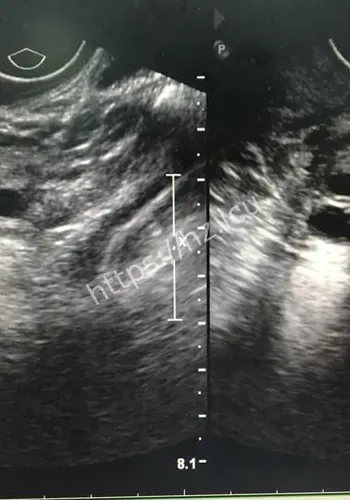

对观众来说,这类热点的影响,往往体现在它会不会改变自己对22厘米肌瘤致孕妇子的判断,或者会不会影响后续生活中的选择与讨论。检查揭示出一连串环环相扣的罕见致命危机:一个大小约为13.212.822.4厘米的巨大肌瘤,上缘顶至剑突,左右分别霸占整个腹腔,甚至超出超声探头的单一切面探测范围,并且提示血运丰富。因肌瘤推挤,子宫发生罕见的“箝闭”,即子宫体向后倾倒、死死卡在直肠窝内,宫底位置低于宫颈外口,整个子宫呈“倒置”状态。